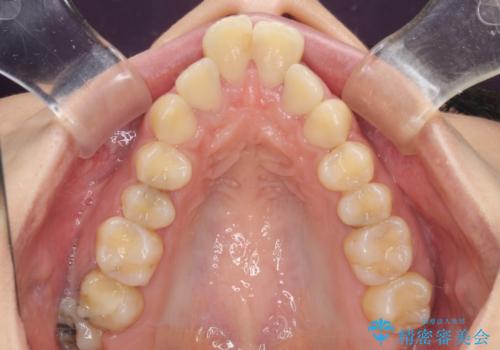

舌の突出癖が顕著で、上顎歯列は完全なV字型となっている状態でした。

どこまで口元の突出感を改善できるのか不安でしたが、舌のトレーニングをしっかりと行ってくださり、我々も驚くほど劇的に改善することができました。